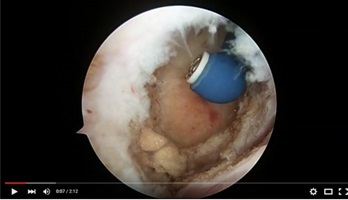

Arthroscopy 2 Surgery - Med X Change

Surgical Video - Med X Change